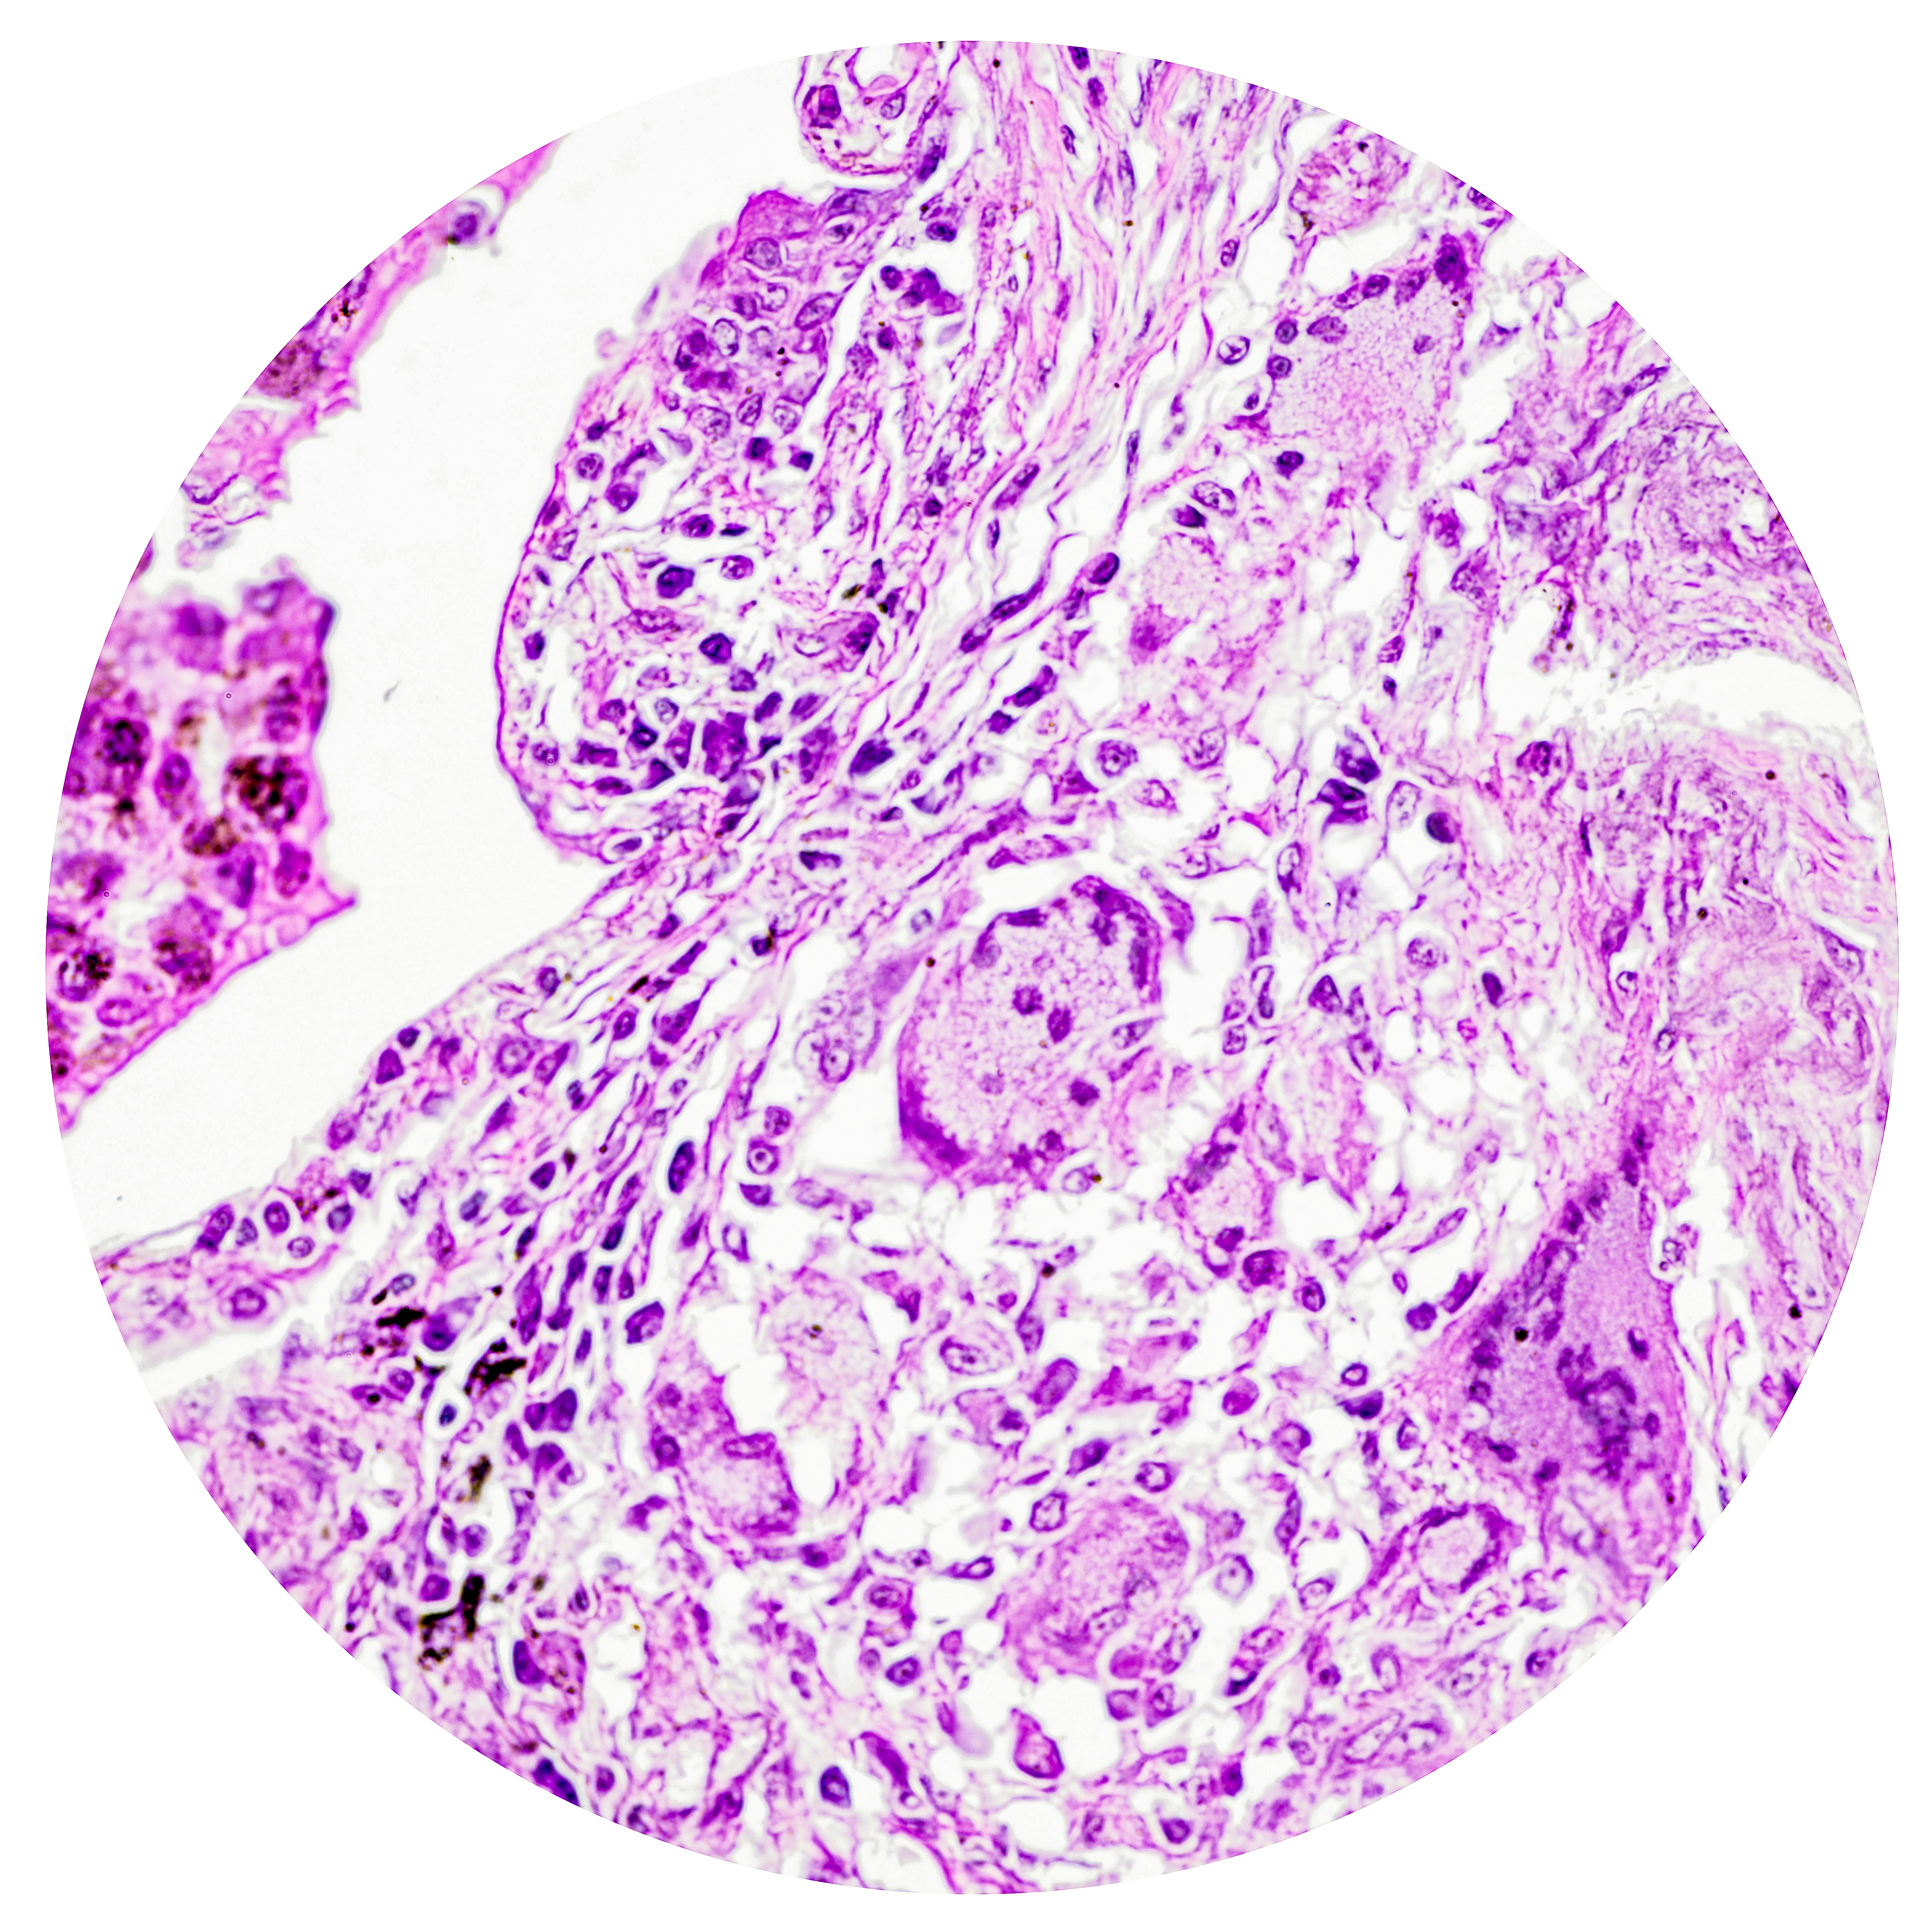

Tuberculosis

Granulomatous Inflammation

Granulomas | collections of modified macrophages surrounded by rim of lymphocytes. Other elements include vascular elements, fibroblasts, collagen, PMNs, and plasma cells

Production of type I collagen surround tubercle providing strong capsule and preventing spread of bacterium

Giant Cells

Fused macrophages, multi-nucleated

Langhans’ Giant Cells | nuclei arranged in horseshoe formation around periphery (characteristic of TB)

Foreign Body-Type Giant Cells | scattered nuclei throughout cell body

Caseous Necrosis

Cell death forming amorphous protein mass with consistency of ‘cream cheese’

Diseased State